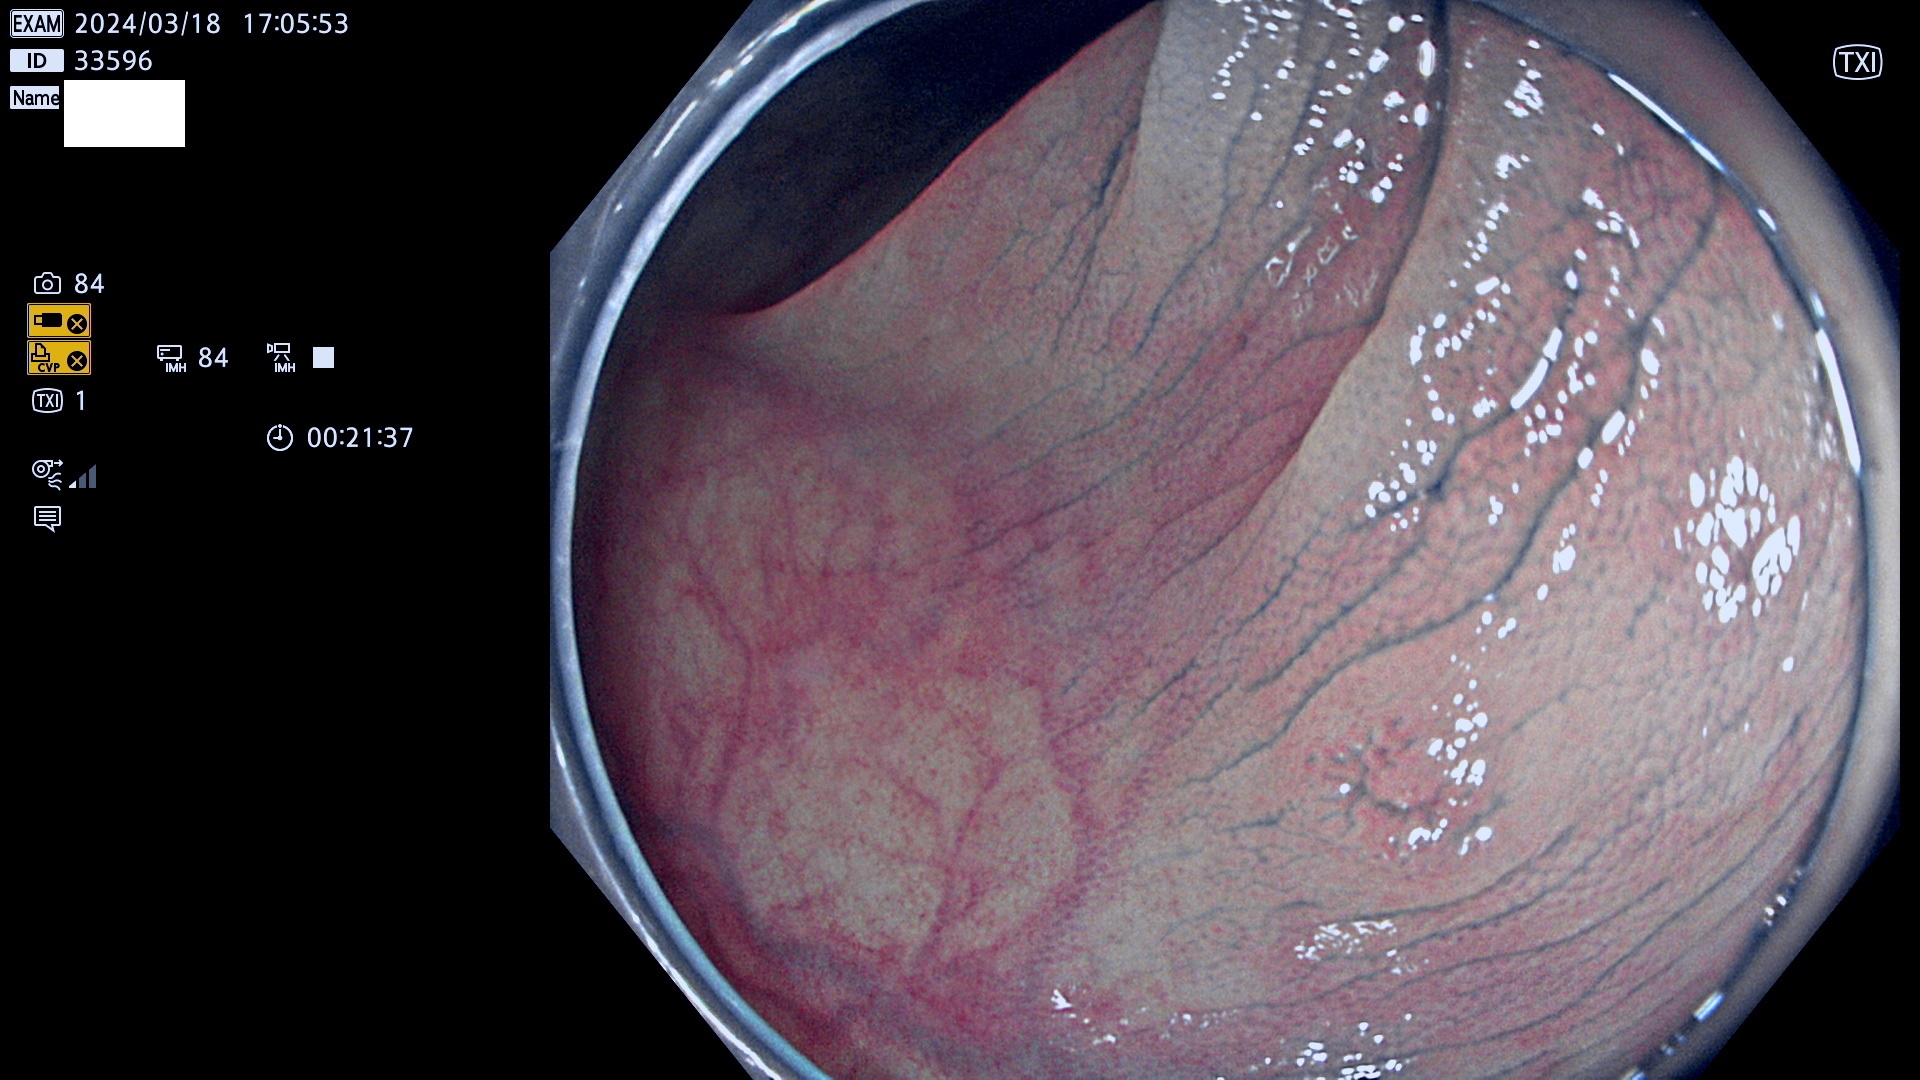

表面型腺腫(Flat Adenoma)の中で、完全に平坦な物をUb、陥凹している物をUcと呼びます。平坦隆起型(Ua)よりも、発見が難しく危険な病変です。

ビランと鑑別の困難な腺腫